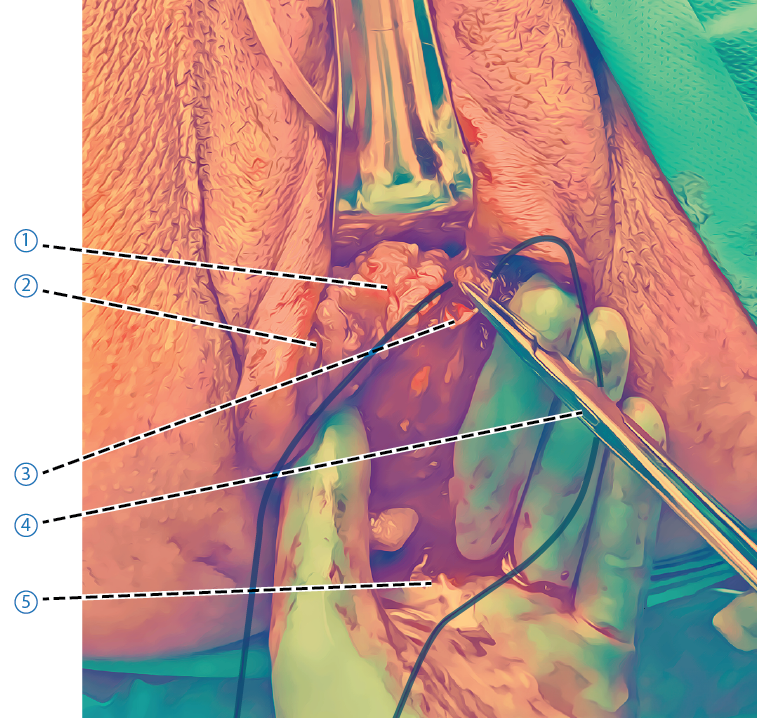

Vid suturering av vaginas bakvägg ska man hålla fingret i rektum och lyfta upp väggen. Använd Allis’ peang för att ta tag i och identifiera muskler och muskelfästen för att se och känna var de hör hemma.

- Rektovaginala fascian och m puboperinealis. Identifiera rektovaginala fascian genom att lyfta upp bakre vaginalväggen med fingret i rektum och använd Allis’ peang för att dra fram fascian under vaginalslemhinnan. Rektovaginala fascian ska sutureras och sedan adapteras mot m puboperinealis från sidorna mot medellinjen. Den ska sutureras i ett eget lager med suturmaterial med medellång resorptionstid (t ex Vicryl® eller Polysorb® 2/0)

- Vaginalslemhinna

- Hymen

- Rektovaginal fascia

- Nålförare

- Finger per rektum

- Inre delar av perinealkroppen (m transversus perinei profundus)